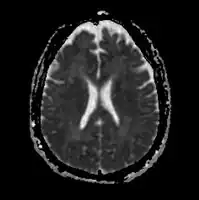

-

Acute severe hepatic encephalopathy -

Acute severe hepatic encephalopathy